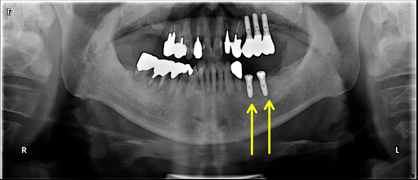

矯正 (女性/城南区)

- 治療前

- 治療中

- 治療後

治療を受けての感想

奥歯の移動の矯正時にインプラントを入れてもらいました。

治療は1年くらいかかかると聞いていましたが、ぴったり1年で終わってよかったです。

治療中は口内写真などできちんと説明してもらいわかりやすかったです。

治療前よりかみ合わせがよくなったように思います。ありがとうございました。